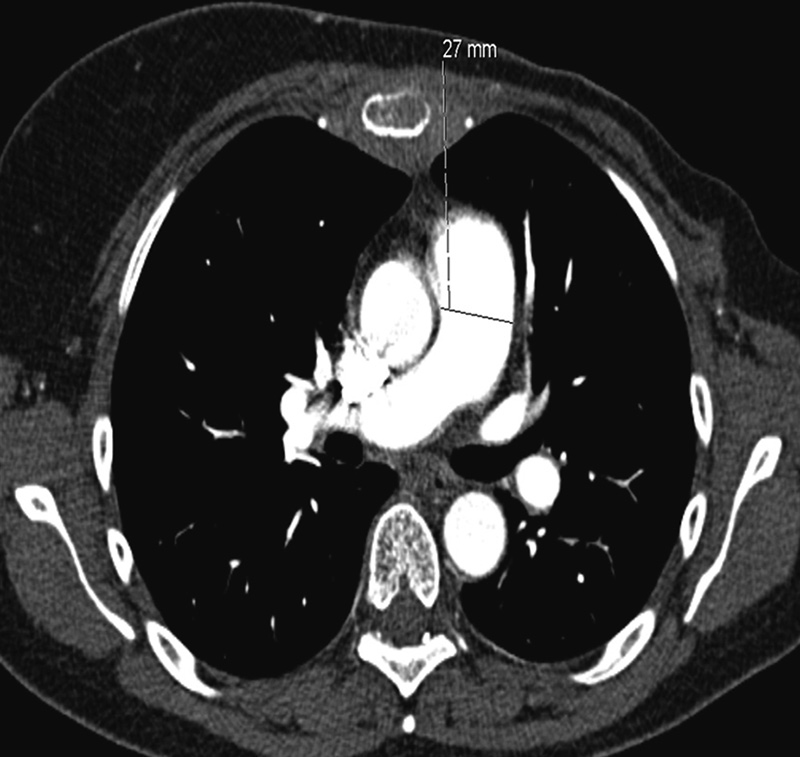

Pga. fall i CRP (fra 123 mg/l til 103 mg/l) samt lett subjektiv bedring av symptomer ble pasienten i første omgang observert, uten behandling med antibiotika. CT av lungearterier var negativ for lungeembolier, men viste vid truncus pulmonalis (33 mm i motsetning til 27 mm ved foregående undersøkelse) som ga mistanke om pulmonal hypertensjon. For øvrig ble det påvist beskjeden vekst av metastaser.

CT thorax 16. innleggelsesdag viste ytterligere utvidet truncus pulmonalis, 37 mm (fig 2) samt tilkomne spredte, konsoliderende fortetninger i venstre lunges overlapp. Sammenliknet med tidligere EKG viste nytt EKG funn som ved høyrebelastning samt QR-mønster i V₁, negativ T i V2 og markert R-tap i fremreveggsavledningene. Pasienten ble henvist til ekko cor, som ble planlagt neste dag. Fra samme dag ble hun tiltakende takykard og hypotensiv og ble etter hvert overflyttet til lungepostens overvåkingsavdeling for respirasjonsstøtte med BiPAP. Morgenen 18. innleggelsesdag (ca. ti uker etter aller første innleggelse for dyspné) fikk pasienten plutselig respirasjonsstans og var ikke kontaktbar. Avansert hjerte-lunge-redning ble igangsatt, men uten at man lyktes i å gjenopprette egensirkulasjon. Pasienten ble erklært død ca. 30 minutter etter oppstart av resuscitering.